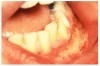

Fig 4. Lidocaine Ointment–induced Cytotoxic Reaction.

Figure 4

Stomatitis and ulcerative stomatitis represent cytotoxic reactions to topically applied agents, e.g., LAs; or may result from the systemic administration of cytotoxic drugs, e.g., antineoplastic agents, which damage not only tumor cells, but all rapidly dividing normal cell populations.14,16 The degree of tissue damage depends on the specific agent, dosage, dosage schedule, and patient-related variables. The lesions may appear as erythematous macules, patches, papules, plaques, or diffuse ulcerations (Figure 3 and Figure 4).